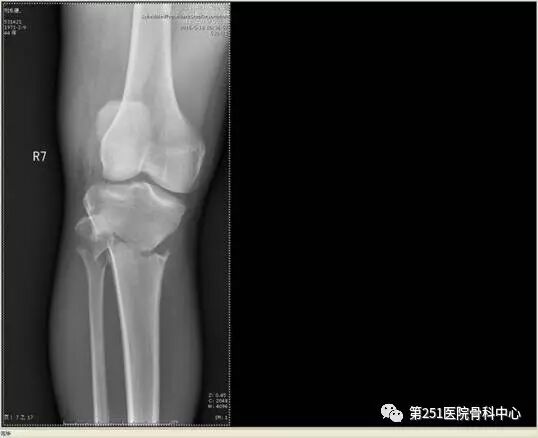

病例1:男性,40岁,车祸伤,胫腓骨多段骨折。